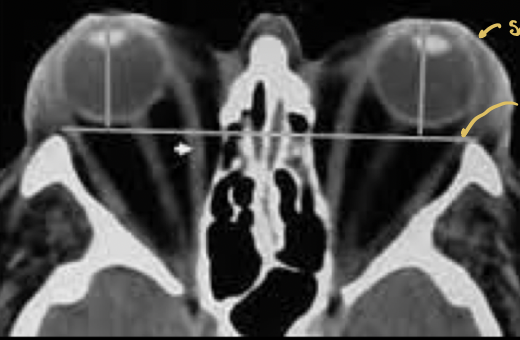

8

Q

¿qué enfermedad sospechas?

A

Orbitopatía tiroidea